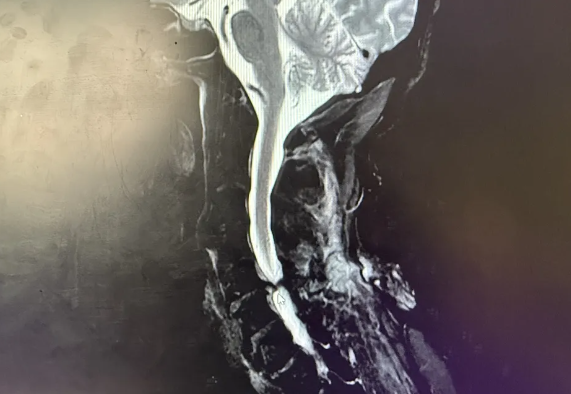

(术前影像)

“时间就是生命,对于脊髓损伤患者更是如此!” 半月前遭遇不幸的刘大叔(化名)——急性颈脊髓损伤导致双下肢完全瘫痪、感觉消失、上肢麻木,生命与功能悬于一线。得益于家属的及时送医和我院急救绿色通道、骨科团队争分夺秒的精准手术(前路C5/6椎间盘切除+椎管减压+融合内固定术),成功解除了脊髓的“致命压迫”,为神经功能的恢复赢得了最宝贵的“黄金时间窗”。